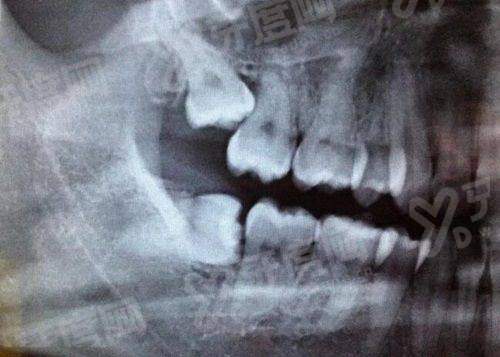

北京倪氏口腔倪以亮在隐形矫正过程中,能够根据患者牙齿移动情况及时调整矫治器,对于复杂病例,可通过分步设计矫治器,实现牙齿的精细移动,达到理想的矫正效 果;是注重咬合关系的调整,不仅关注牙齿排列整齐,还重视上下颌牙齿的咬合功能,确保矫正后牙齿既能美观又能正常行使咀嚼功能;对于隐形矫正过程中可能出现的牙齿脱轨等问题,能够及时发现并采取有效措施进行处理,保护矫正过程顺利进行。

北京倪氏口腔倪以亮对于成人骨性错颌畸形患者,能够结合正畸-正颌联合治疗的理念,与颌面外科医生协作,制定综合治疗方案,帮助患者改善面部轮廓和咬合关系;北京倪氏口腔倪以亮在青少年生长发育高峰期,能够抓住矫正的黄金时期,通过功能矫治器等手段引导颌骨正常发育,预防错颌畸形的进一步发展,取得较好的治疗效 果;北京倪氏口腔倪以亮对于二次矫正患者,能够分析首次矫正失败的原因,制定针对性的矫正方案,解决牙齿复发、咬合不良等问题,帮助患者重新获得整齐的牙齿。